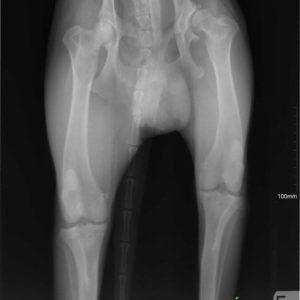

Köszönjük szépen Alexander Englert-nek, hogy Mex diszplázia műtéti költségét finanszírozta! Még 2 és fél hónap rehabilitáció és kereshetünk neki új gazdit! Category: HírekBy Csillag Alexandra2017-09-14 Share this post Share on FacebookShare on Facebook Share on XShare on X Author: Csillag Alexandra http://www.ebarvahaz.hu Post navigationPreviousPrevious post:SnowNextNext post:Közeleg a tél!Related postsPályázati eredmény2026-03-17Tami és a babák2026-01-22Cuki újoncaink2025-10-27IV. TÖKéletes nap az EbÁrvaházban2025-10-17Kutyás családi és nyílt nap a Kraft SE szervezésében2025-09-01Karamell kisgengszter berobbant a menhely életébe <32025-08-05